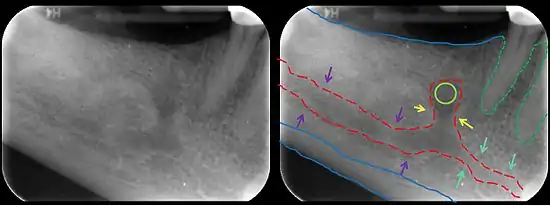

![]() The permanent teeth, viewed from the right. The external layer of bone has been partly removed and the maxillary sinus has been opened. | |